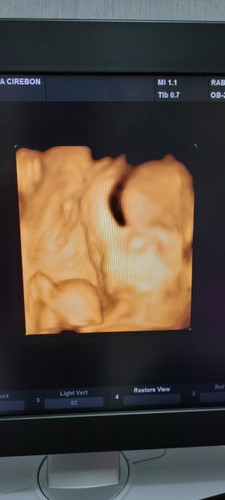

Bun mau tanya, ini hasil usg 6 bulan. Kenapa bentuk kepala nya gtu ya bun, agak khawatir. Ada yg tau

dokternya bilang itu kelainan atau bukan bu?

dokter nya bilang normal dan sehat bun